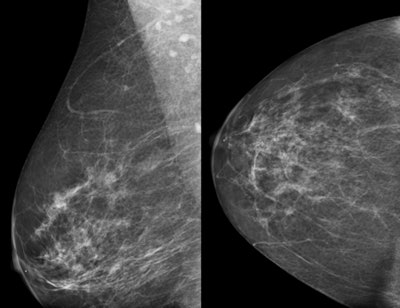

| Above, normal screening mammogram of contralateral right breast in patient with newly diagnosed left breast cancer and "not dense" breast tissue. Below, MRI reveals suspicious mammographically occult mass in right breast; MRI-guided biopsy yields diagnosis of contralateral infiltrating ductal carcinoma. All images courtesy of Dr. Reni Butler. |